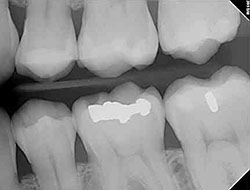

Digital X-rays

Using the most advanced dental technology possible is just as important as staying up-to-date on the latest treatment techniques. Because our practice is dedicated to providing you with the safest and most convenient treatment options available, we utilize advanced digital X-ray technology in our office.

Digital X-rays provide several advanced imaging options designed to save time, provide clearer dental photos, and expose patients to less radiation than with traditional X-ray technology.